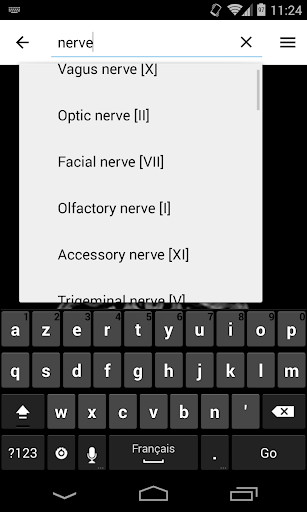

*Find your anatomical parts more easily thanks to the new, more intuitive and powerful search feature